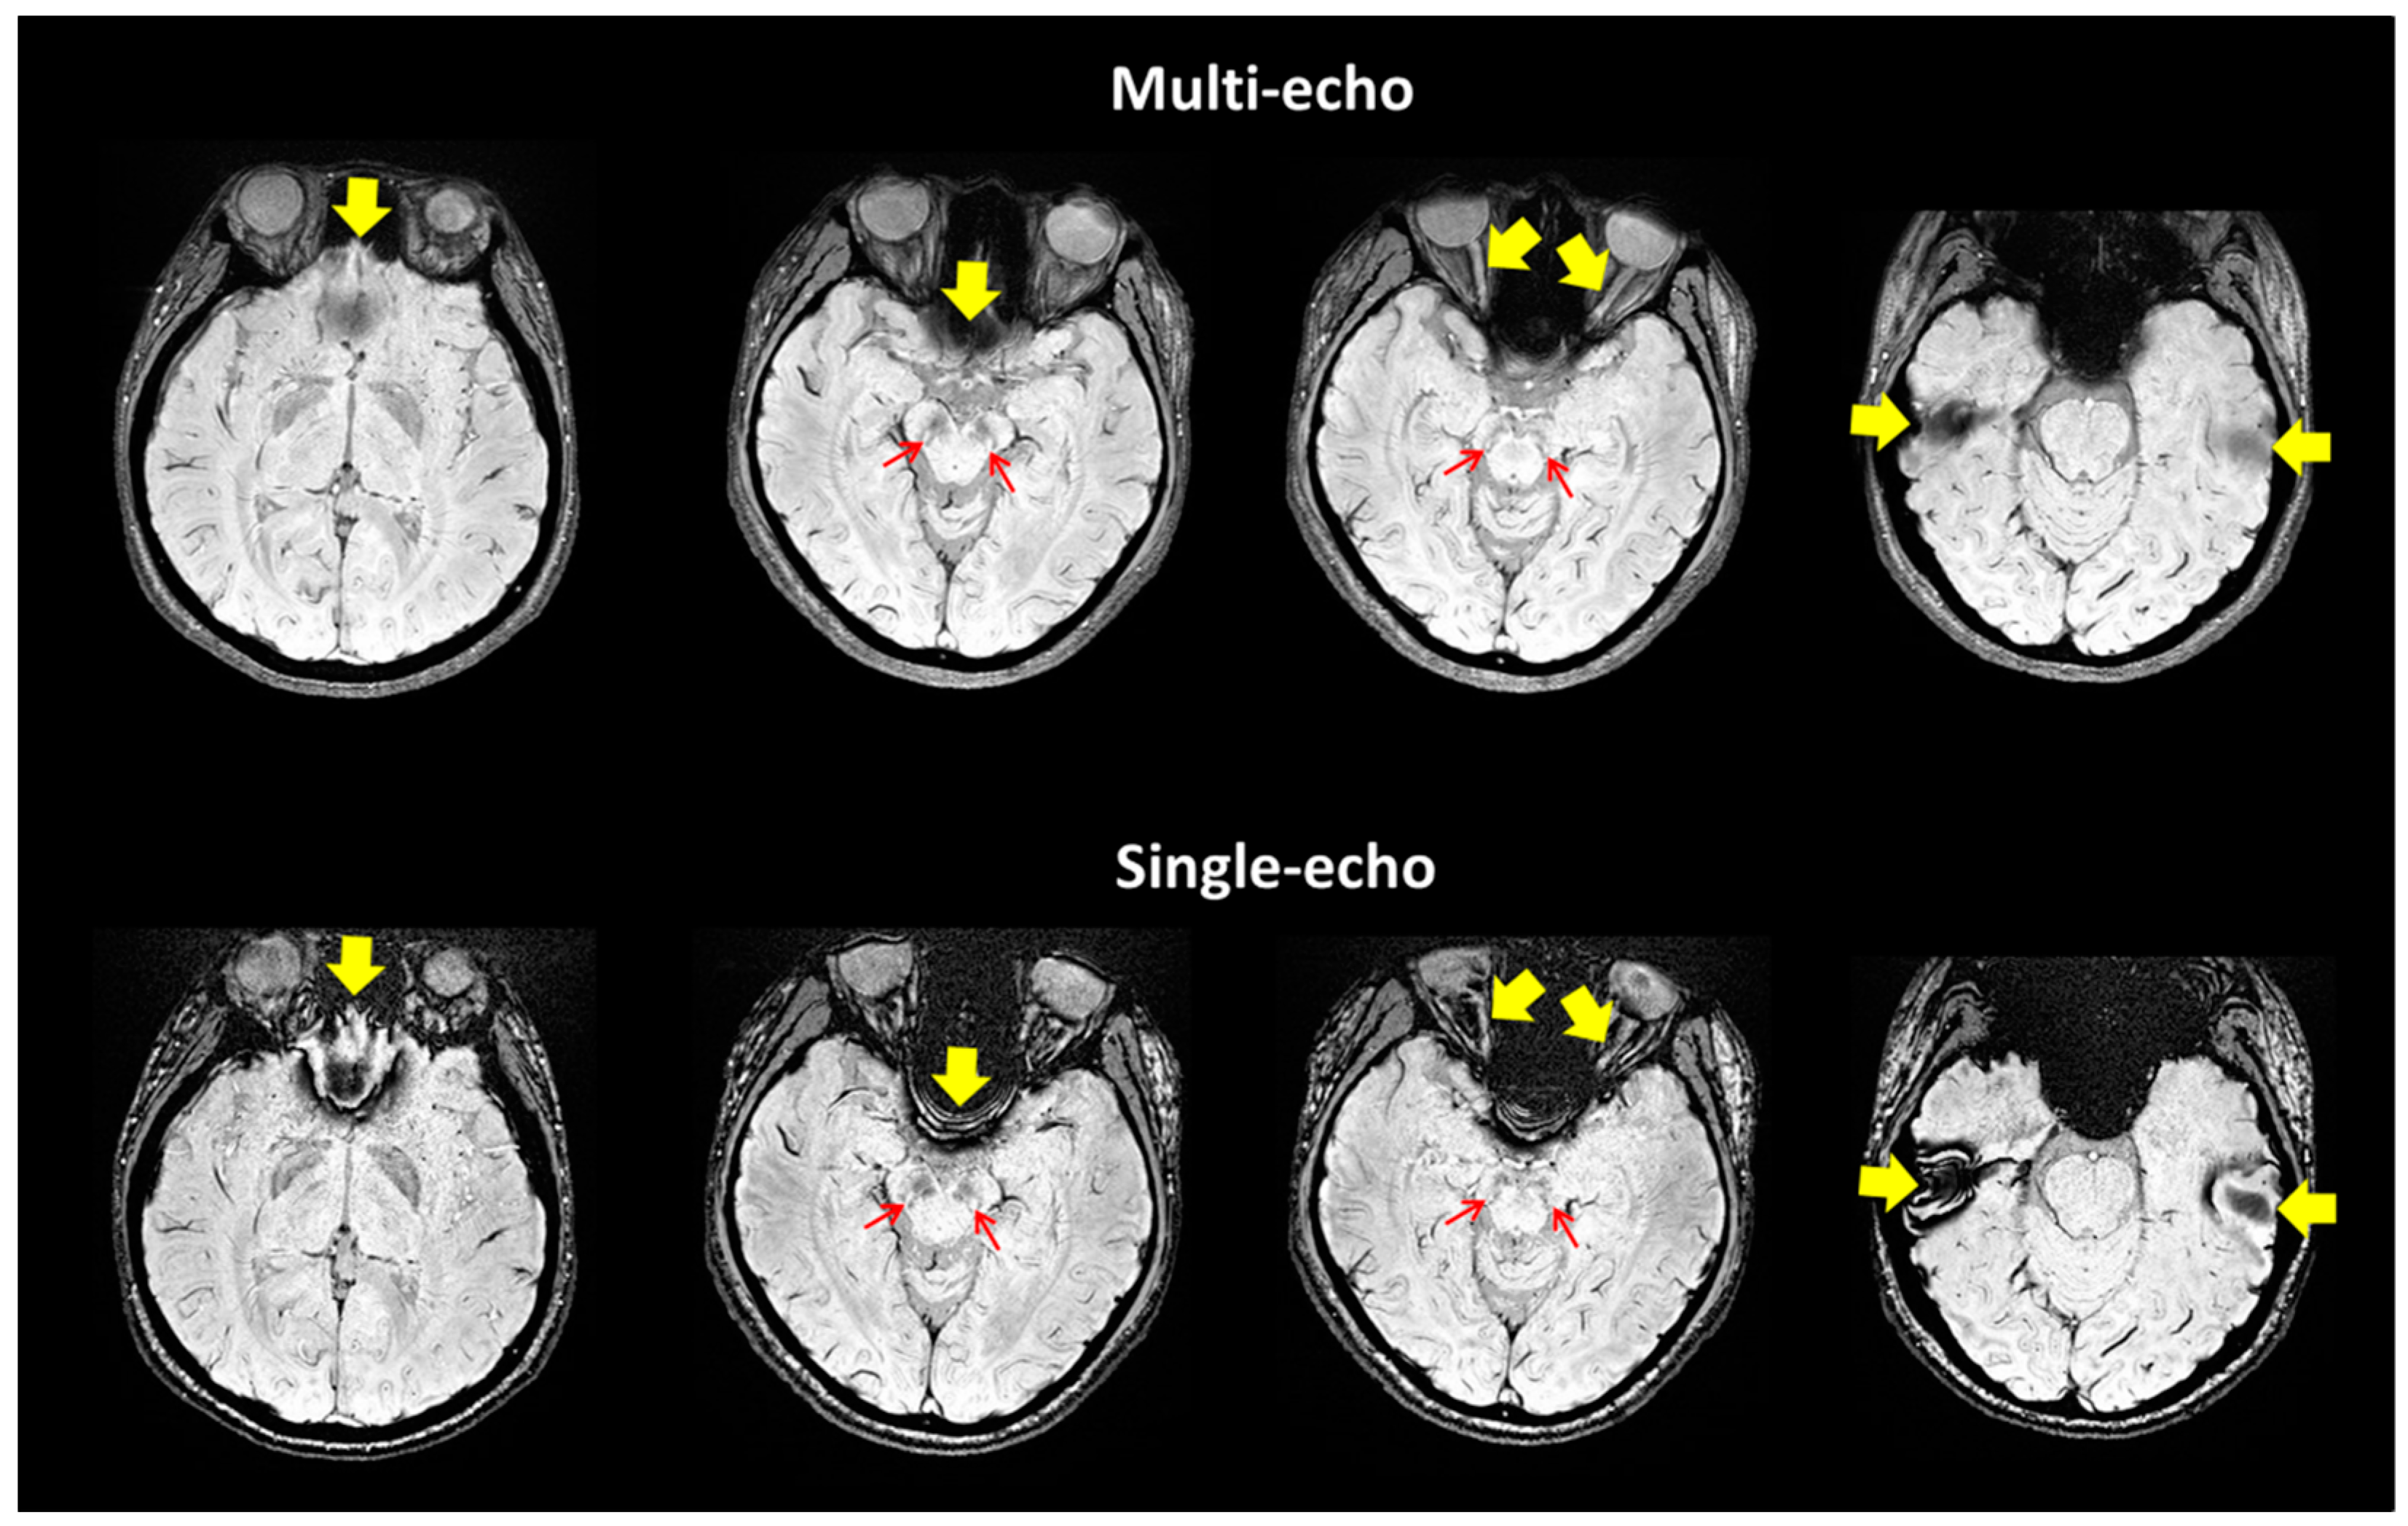

2.2. Imaging Protocols

2.3. Imaging Data Analyses

3. Results

4. Discussion